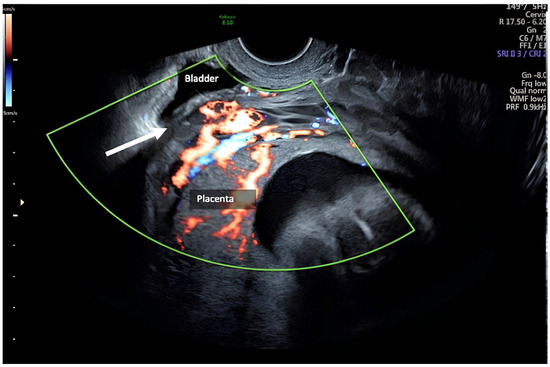

| Zermano S. et al. | 2024 | Yes | Yes | Yes | 24 5/7 | ||

| Zermano S. et al. | 2024 | 29 1/7 | No | Yes | Yes | Yes | |